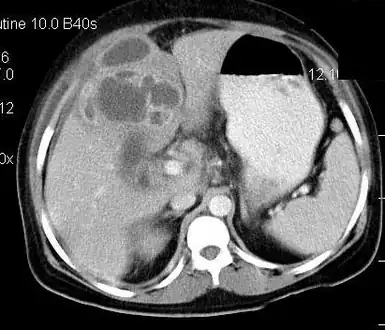

Contrast enhanced computed tomography of the abdomen is showing gall bladder empyema with perforation and formation of liver abscess.